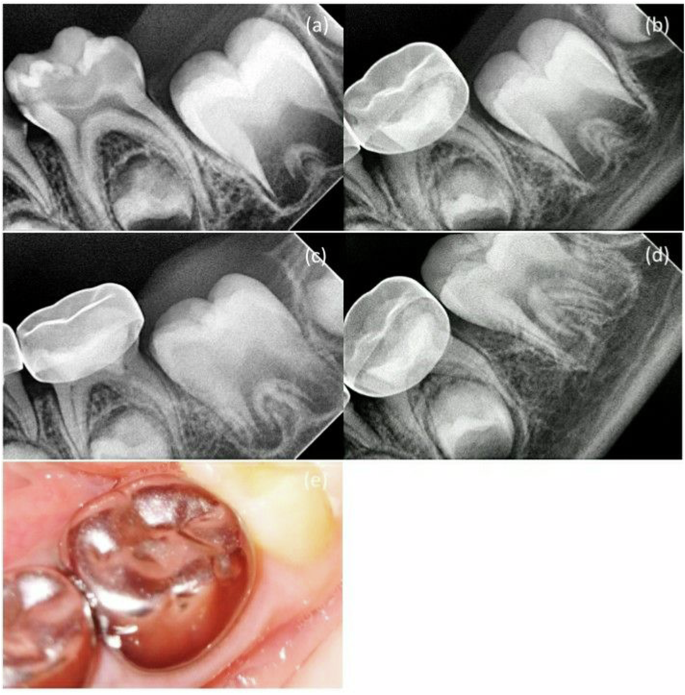

Both MTA + NaOCl gel and MTA + DW groups demonstrated a 90% success rate in clinical outcomes after three months of follow-up, with two cases (10.0%) reporting pain on percussion in both groups (Table 2). Furthermore, MTA + NaOCl gel group’s radiographic success rate was 95%, as one case (5.0%) showed internal root resorption, external root resorption, and widening of the periodontal ligament (Table 2).

Conversely, MTA + DW group achieved a 100% radiographical success rate at the three-month follow-up (Table 2). At a 6-month follow-up, the clinical success rate remained 90% for both groups. However, in MTA + DW group, one case (5.0%) experienced internal and external root resorption, resulting in a radiographical success rate of 95%.

Furthermore, in MTA + NaOCl gel group, a canal obliteration was detected in one case which was not regarded as a radiographic failure. At the 12-month follow-up, the clinical success rate for both groups remained to be 90%, while the radiographic success rate for MTA + NaOCl gel group also remained at 95%. In contrast, MTA + DW group experienced a decrease in radiographic success rate to 85% due to the diagnosis of internal root resorption in two cases (10.0%). Nevertheless, no statistically significant difference was observed in the clinical and radiographic success rates between the two groups at different follow-up intervals (p > 0.05) (Tables 2, 3, 4), suggesting that the MTA + DW group did not outperform the MTA + NaOCl gel group in improving treatment outcomes (Figs. 2, 3, 4).

The study found that the WMTA + NaOCl gel group showed canal obliteration in one case, indicating tooth vitality rather than failure, as it resulted from odontoblast activity [51, 52]. Histological findings supported this, with initial odontoblastic disorganization at 7 days but normal tissue structure after 90 days [7]. The group also exhibited small calcifications, 87.5% at 7 days, reducing to single calcifications by 90 days, unlike the control group, which showed no pulp calcification [7]. The WMTA + NaOCl gel performed comparably to WMTA + DW, with no significant difference in treatment outcomes [7]. Despite initial inferior properties, the NaOCl gel achieved similar performance after one month [7]. Thus, the null hypothesis was not rejected, confirming that both materials behaved similarly. Zero drop-outs do not mean zero failures. No patients were lost to follow-up. Teeth extracted for resorption were counted as failures, not drop-outs, especially with strict inclusion criteria.